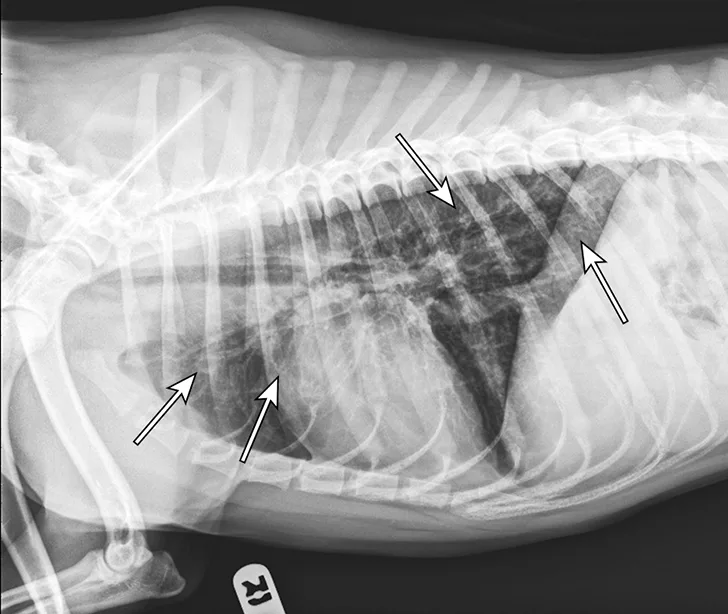

Thoracic radiographs showing a characteristic diffuse, patchy bronchointerstitial pattern (arrows)

Thoracic radiographs revealed a moderate, diffuse, bronchointerstitial pattern (Figure 1). The cardiac silhouette, pulmonary vasculature, and extrathoracic structures were normal. Airway sampling via bronchoscopy was recommended based on radiographic findings. CBC and serum chemistry profile were performed prior to sedation. Serum chemistry results were within normal limits. CBC revealed leukocytosis (24.3 x 103/µL; normal range, 4.9-17.6 x 103/µL) characterized by marked eosinophilia (10.4 x 103/µL; normal range, 0.07-1.49 x 103/µL), monocytosis (1.4 x 103/µL; normal range, 0.13-1.15 x 103/µL), and band neutrophilia (729/µL; normal range, 0-170/µL). Heartworm antigen test was negative.

Thoracic radiographs are generally characterized by a diffuse bronchointerstitial pattern with peribronchial cuffing and thickening of the bronchial walls. In some cases, bronchiectasis or alveolar infiltration may be observed.2,6-8 Occasionally, patchy pulmonary opacities create a nodular appearance.4 Radiography is critical for ruling out other common causes of cough and/or acute respiratory distress. Concurrent disease processes (eg, cardiomegaly, tracheal collapse) can complicate diagnosis.